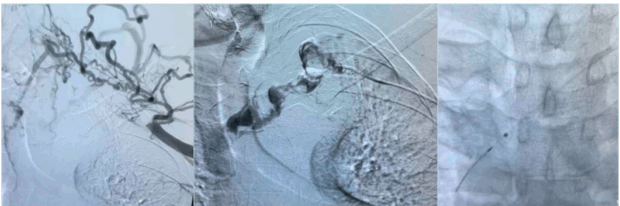

Catheter-directed thrombolysis (CDT) : This technique involves infusion of tissue plasminogen activator (tPA) via multi-side-hole catheter inserted within the thrombus over 12 to 24 hours. During this time, the patients require one-on-one care in a high dependency unit (HDU) or intensive treatment unit (ITU) bed (Figures 8 and 9).

Figure 8. Initial venogram shows thrombosed axillary-subclavian vein (left image), selective venogram beyond the thrombus (middle image), and fluoroscopic picture confirming location of the tip of the infusion catheter distal to the thrombus (right image).

After thrombus removal, immediate completion venography with or without IVUS is recommended to confirm the flow restoration; detect any residual webs, stenosis, or intimal hyperplasia; and to guide decisions about the need for additional decompression or revascularization procedure (Figure 10).